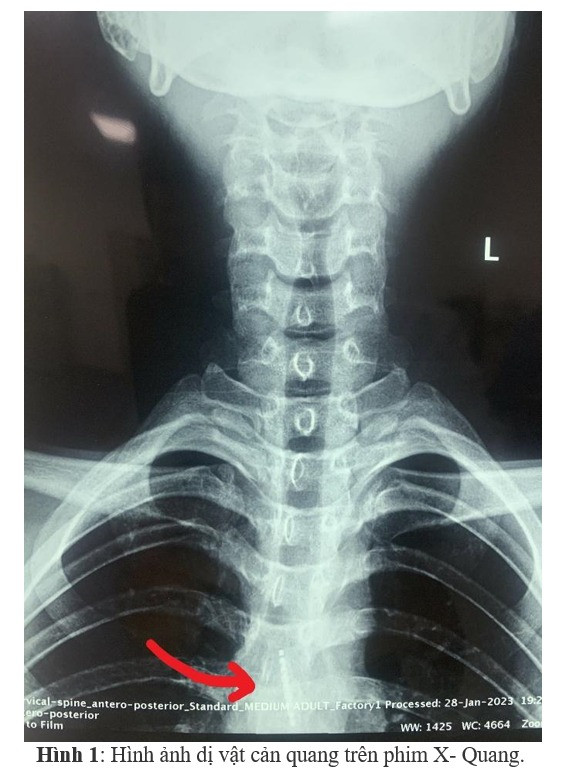

Sau khi vào viện, bệnh nhân được đánh giá toàn trạng, khám nội soi tai - mũi - họng, chụp phim X-quang để chẩn đoán, phát hiện dị vật cản quang thực quản đoạn ngực - bụng. Bệnh nhân đã được gây mê, đặt ống cứng soi trực tiếp thực quản lấy dị vật.